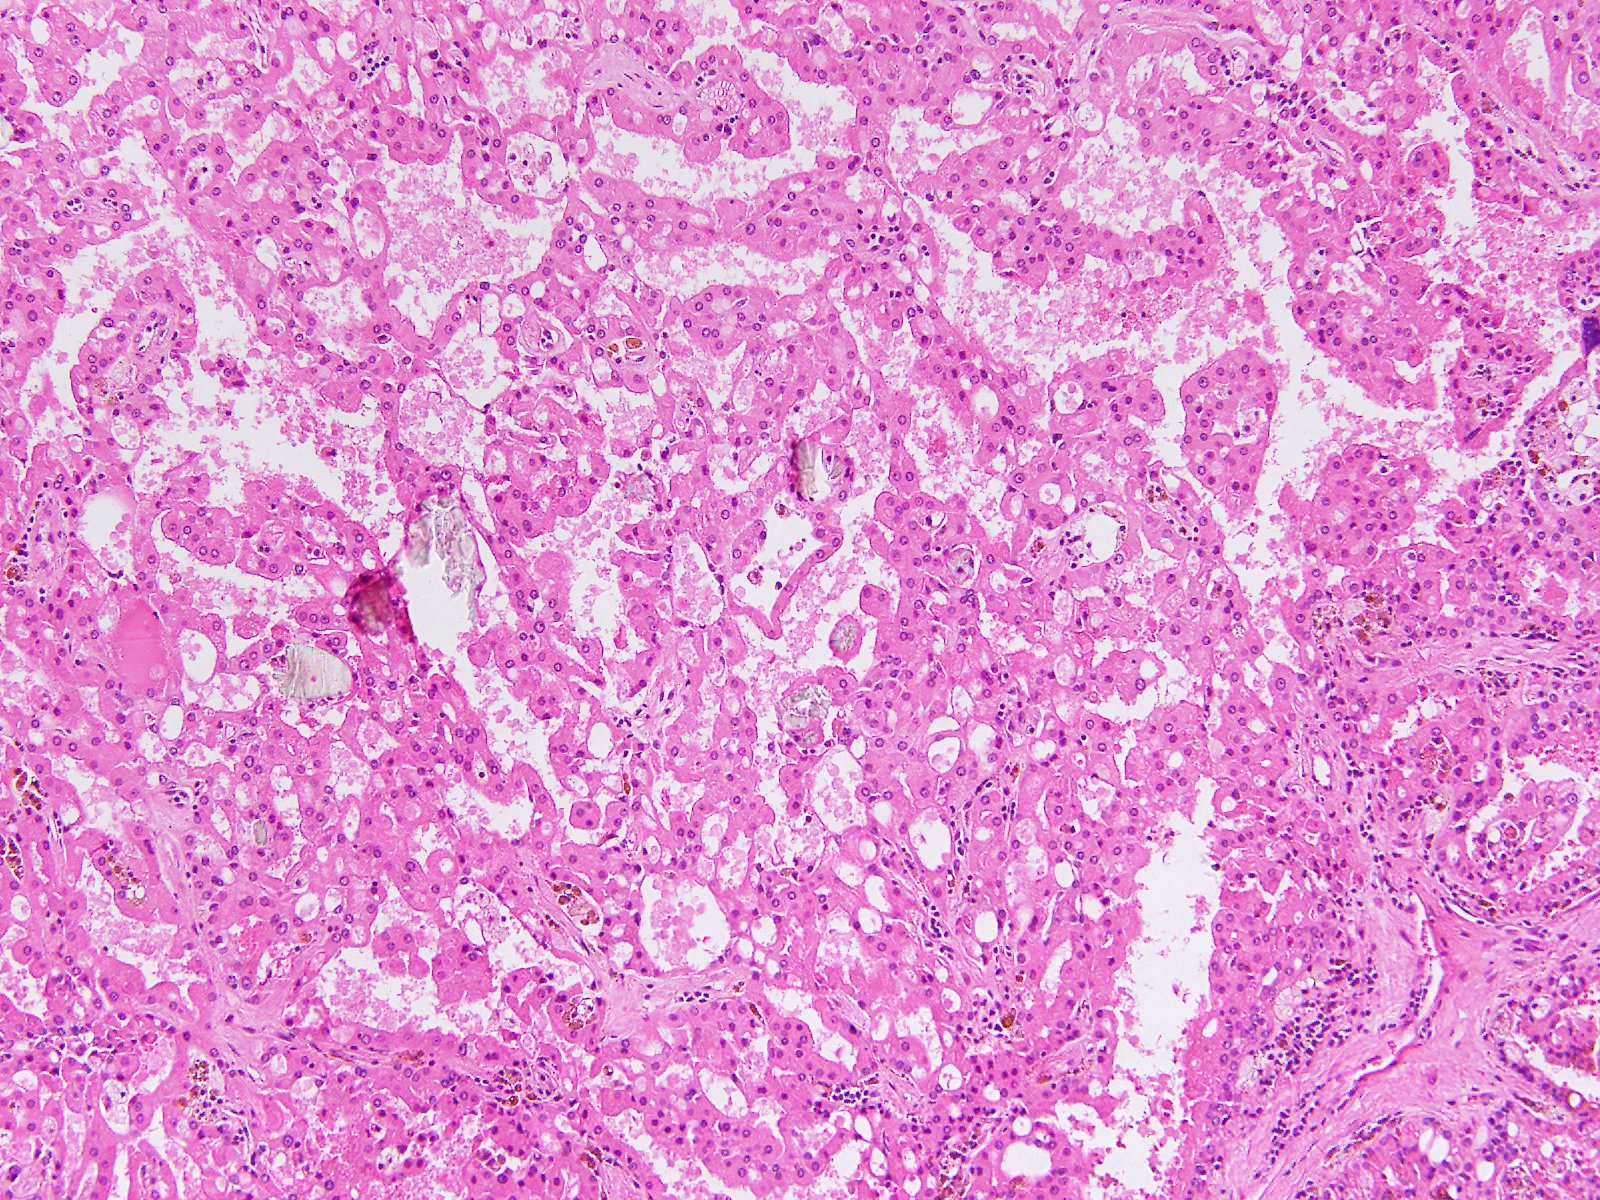

Consensus grade: Acquired cystic disease-associated RCC

Case description (by case creator):